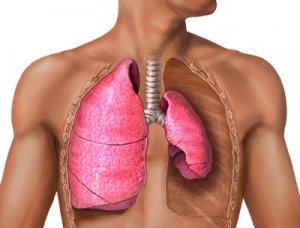

Воспаление легких

Воспаление легких (пневмония) – это сложная инфекционная патология, которая возникает тогда, когда острый бронхит поразил ткани легких.

Заболевание чаще распространяется на детей в связи со слабым иммунитетом.

Эмфизема легких

Осложнения после бронхита в некоторых случаях могут развиваться в форме эмфиземы легких. Хроническое воспаление нарушает обмен газа в легочной ткани, а также ее эластичность.

Альвеолы сильно растягиваются и не могут сокращаться до нормального состояния. Легкие «зарастают» соединительной тканью, что приводит к сужению бронхов.

Начальная стадия эмфиземы характеризуется одышкой при физических усилиях, которая чаще наблюдается в зимнее время.

Если вовремя не назначить лечение, одышка начинает возникать при малейших физических усилиях и даже в состоянии покоя.

У пациента наблюдается короткий вдох и продолжительный выдох. Дыхательные сокращения грудной клетки уменьшаются, вовлекая в процесс мышцы груди и шеи. В качестве основных симптомов болезни выделяют цианоз, выпячивание надключичных областей, уплотнение грудной клетки, расширение межреберных участков.

Диффузный пневмосклероз

Диффузный пневмосклероз, как осложнение бронхита, характеризуется поражением всей площади одного или обоих легких, происходит изменение структуры легочных тканей.

Далее начинается разрастание соединительной ткани, что ведет уменьшению легких и затруднению кислородного снабжения организма.

Опасность болезни заключается в том, что на ранних стадиях она протекает без симптомов.

В данном случае пациент может жаловаться на легкую одышку во время физической нагрузки, утомляемость и сухой кашель.

С прогрессированием болезни у пациента начинает болеть спина на уровне грудной клетки, наблюдается слабость, ухудшение самочувствия, ноющая боль в области груди.

Иногда могут наблюдаться признаки цирроза легкого, которые проявляются деформацией грудной клетки и атрофией межреберных мышц.

Несмотря на серьезные патологические процессы в сфере органов дыхания, наибольшие разрушительные явления при гриппе происходят в сердце и сосудистом русле. Это главное звено патологических процессов. Происходит значительное повышение проницаемости стенок сосудов, отекают слизистые оболочки сердечных клапанов и предсердий, возникают масштабные кровоизлияния в ткани легких, сердца, печени, почек и головного мозга. При этом воздействие опасных токсинов более всего проявляется на кровеносной системе: